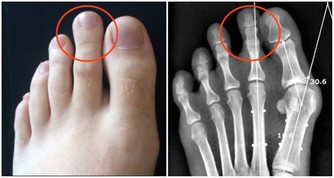

如果主子的眼皮跳逐漸加重,影響到整個眼部,那你就要注意某些疾病了,像近視、遠視、散光等眼部疾病,還有神經受到壓迫、大腦病變等原因也會引起眼皮跳哦。

這些原因引起的眼皮跳,不僅發作頻繁,而且跳動幅度還很大,有些人甚至會連額頭、嘴角都一起抽動,這種時候你一定要及時治療,以免出現嘴歪眼斜的現象。